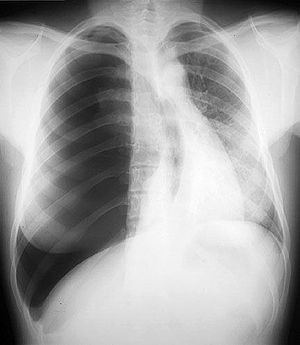

45yo non-smoker presents with rhinorrhea and sneezing

View

DX

View: PA

DX: carcinoid tumor